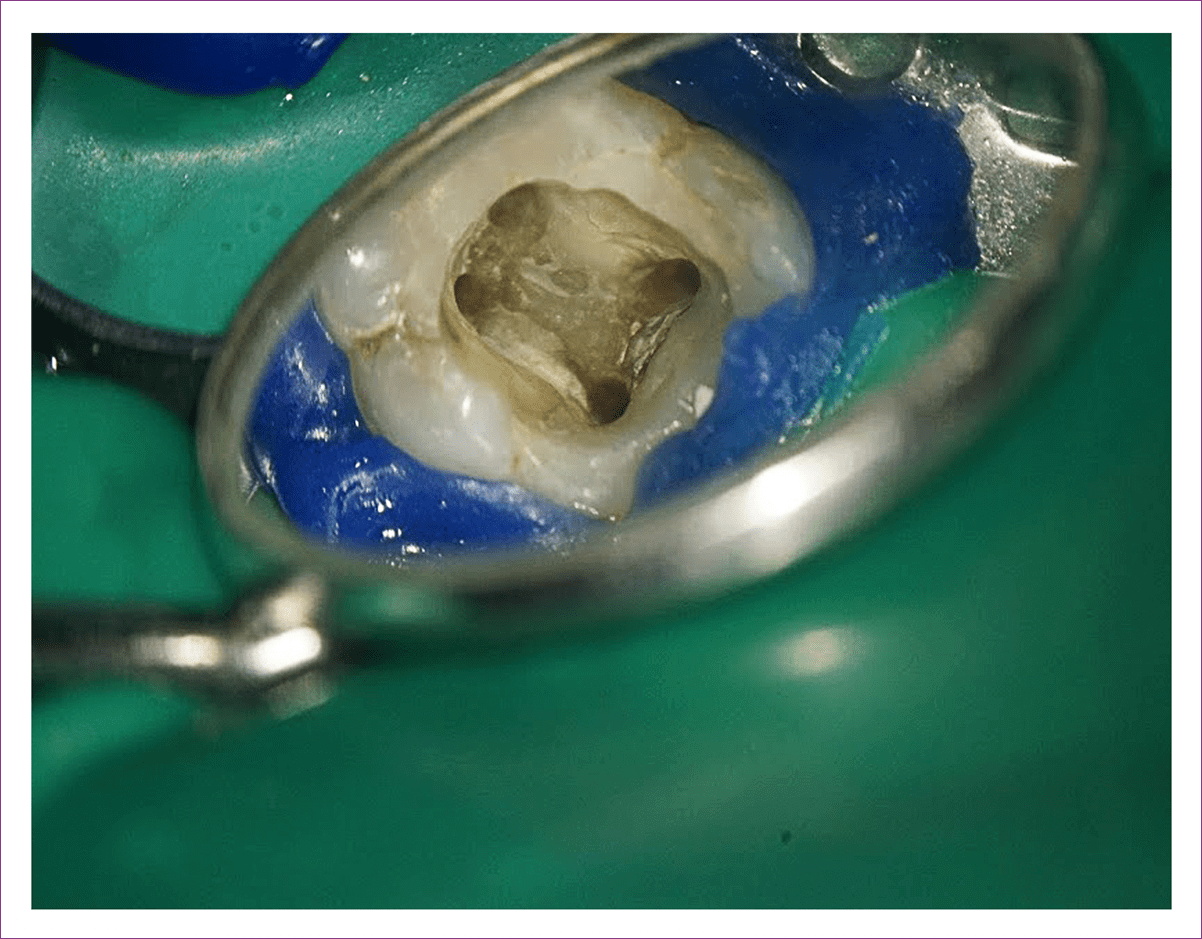

A többszörös nagyításban ugyanis a szakember minden foggyökércsatornát tüzetesen átvizsgálhat, hogy megtalálja a gyulladás (és fájdalom) kiváltó okát, majd el is távolítja azt.